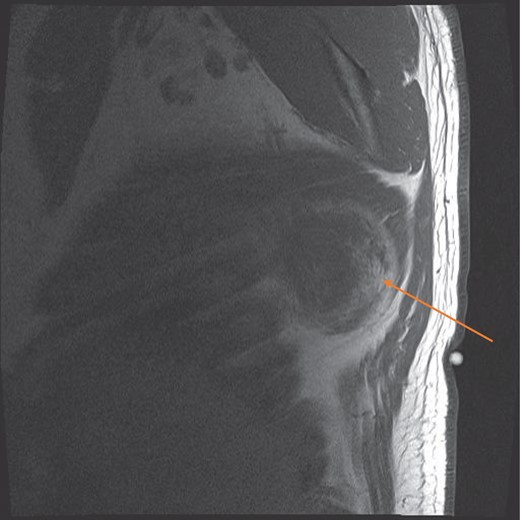

MRI confirmed the diagnosis and showed a second lesion on his left side, also at the infrascapular area (Figs 1–3). The patient had not complained of any symptoms to his left side or his left shoulder joint. After an extensive discussion with the patient and his family, we decided on a computerized tomography (CT) guided true cut biopsy to confirm the diagnosis (Fig. 4).

MRI sagittal view showing the circumscribed right sided tumour with a pseudocapsule, at the infrascapular region (orange arrow).